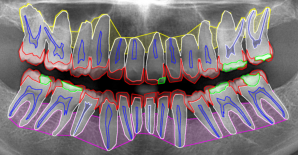

The proposed dataset, TL-pano [banks2025tlpano], consists of 194194 anonymous panoramic radiographs taken from 194194 patients with various backgrounds, ages, and dental hygiene practices, from Universidade de São Paulo, São Paulo, Brazil. Images were annotated with instance level multiclass and overlapping segmentation polygons, completed by three dental experts of at least 1010 years of experience each, using the VGG Image Annotator [dutta2019vgg]. Images were annotated to indicate structural anatomies of the patients, such as tooth layers, FDI [FDI2001] tooth numbers, composite material, and alveolar bone, an example of which is shown in Figure 1. The majority of classes are annotated in a multiclass scheme, but the tooth layer class was given additional multilabel sub-classifications for FDI tooth numbering and quadrant numbering.

Refer to caption

Figure 1: Cropped image of a panoramic radiograph with overlaid wireframe annotations for tooth layer dataset, of image 002.jpg. Classes include: Composite (green), Enamel (red), Pulp (dark blue), Tooth (light blue), Upper Alveolar Bone (yellow) and Lower Alveolar Bone (pink).